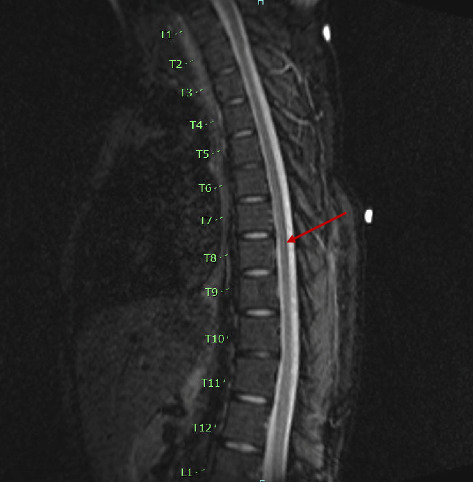

Human T-lymphotropic virus type 1 (HTLV-1), the first oncogenic retrovirus discovered in humans, is primarily associated with two disease entities: adult T cell leukemia-lymphoma and HTLV-1-associated myelopathy-tropical spastic paresis. HTLV-1 has also been implicated in the pathogenesis of various autoimmune rheumatic diseases, and its association with the autoimmune disorders of the gastrointestinal track is less well understood. Our patient, a 26-year-old previously healthy female, presented with recurrent, progressively worsening chronic abdominal pain and persistent liver test abnormalities. Initially diagnosed with acute acalculous cholecystitis and autoimmune hepatitis (AIH), her liver tests continued to exhibit a predominantly cholestatic pattern. This prompted further advanced imaging, and magnetic resonance cholangiopancreatography ultimately confirmed a diagnosis of primary sclerosing cholangitis (PSC). Complicating her condition further, she developed lower extremity weakness, initially attributed to axonal Guillain-Barré syndrome, which unfortunately did not respond to standard treatment. After a year marked by progressive clinical decline with repeated and prolonged hospitalizations due to fever of unknown origin, an extensive diagnostic workup ultimately led to a diagnosis of HTLV-1 myelopathy, along with AIH-PSC overlap syndrome. This case highlights the diagnostic challenges associated with the multisystem involvement of HTLV-1. Notably, our patient's presentation was not consistent with classic HTLV-1 myelopathy rather a subtype with rapidly progressive symptoms and flaccid as opposed to spastic paresis. The association between HTLV-1 infection and autoimmune cholangiopathy is exceptionally rare. To the best of our knowledge, our case represents only the second reported instance of autoimmune cholangiopathy associated with HTLV-1 myelopathy and the first reported case of AIH-PSC overlap syndrome associated with HTLV-1 myelopathy. This underscores the need for heightened clinical awareness of potential hepatic immune manifestations in patients with HTLV-1 infection, even in the absence of classic neurologic symptoms at initial presentation.